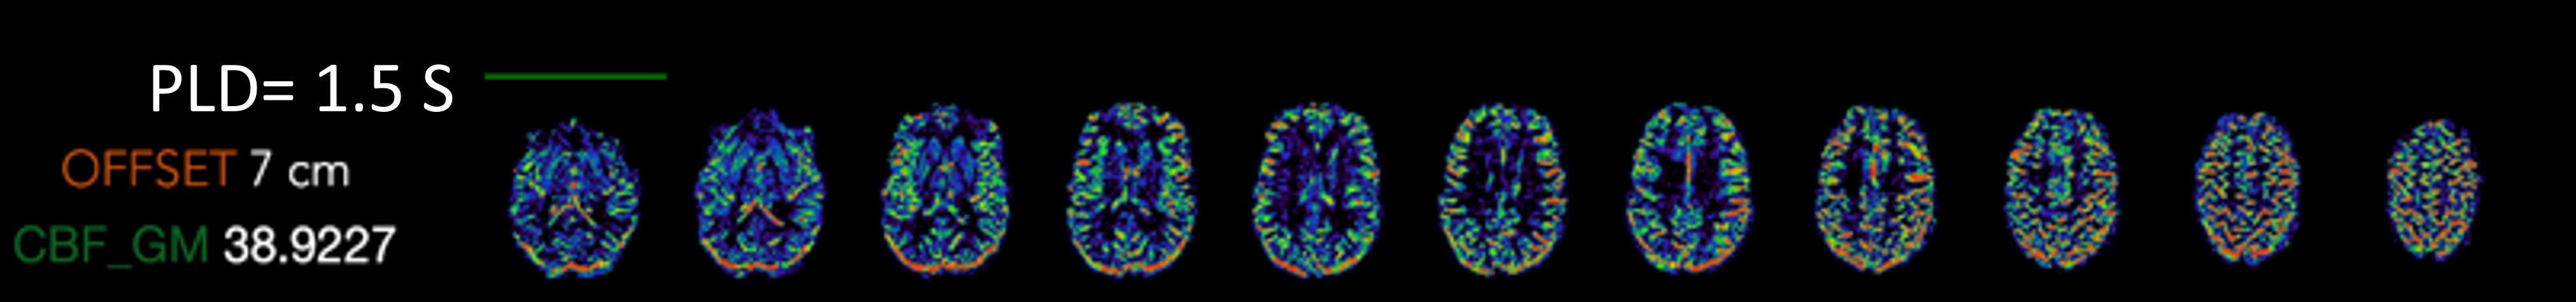

Arterial Spin Labeling

Pseudo-continuous arterial spin labeling (pCASL) allows us to visualize the brain perfusion.

Imaging parameters

- 2x2x3 mm3 resolution, TE=19ms, TR=5060ms, varying post labeling delays (PLD) acquisition time = 3.5min